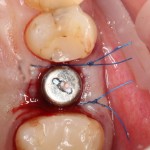

Но в данном случае стабильность хорошая, на имплантат фиксируем формирователь десны, накладываем швы:

Еще один важный момент. Не нужно пытаться стянуть рану и добиваться плотного прилегания десны к формирователю. Любое натяжение слизистой оболочки ведет к ее изменению (прикрепленная десна становится подвижной), а процессы атрофии костной ткани ускоряются. Чем меньше тянем и перемещаем — тем лучше. Поэтому вполне разумно оставить вокруг формирователя открытую рану шириной 0.5-1.5 мм, она нормально заживет вторичным натяжением.